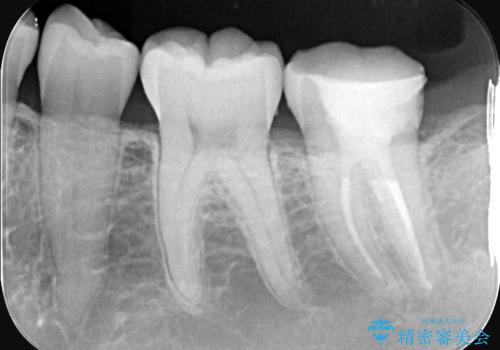

- 昨日からのズキズキとした激しい痛みを主訴にご来院されました。レントゲンおよび歯髄診察の結果、不可逆性の歯髄炎(歯の神経の重度の炎症)と診断。歯を残すことを第一に、まず痛みの原因である神経を取り除く根管治療を提案しました。また、虫歯が歯肉の下まで深く進行していたため、根管治療後に歯周外科処置を行い、最終的に精密なセラミッククラウンで修復する、総合的な治療計画を立案しました。

治療はまず、根管治療から始め、感染した神経を徹底的に除去することで、痛みをすぐに解消しました。再発を防ぐため、ラバーダムや顕微鏡を使って、根管内を丁寧に、そして精密に処置しました。次に、深い部分の虫歯を確実に治療するため、歯周外科処置を行い、治療しやすい環境を整えました。最後に、機能と見た目に優れたセラミッククラウンを作製・装着。根管治療から外科処置、審美修復までを一貫して行うことで、再発リスクの低い、長期的に安定して使える奥歯を取り戻していただけました。